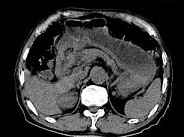

- 单项选择题根据所提供的图像,最可能的诊断是 ( )

A、胃淋巴瘤

B、胃平滑肌瘤

C、胃窦癌

D、胃窦炎

E、以上都不是